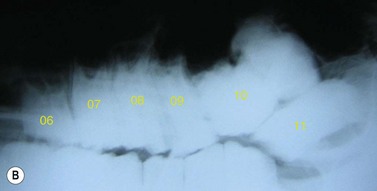

Lateral projection (Figs 13.513.7)

The lateral view is useful to visualize fluid lines and abnormalities of the maxillary or frontal bones or within the paranasal sinuses because the anatomy of the sinuses is not distorted by obliquity of the X-ray beam. The major disadvantage of the lateral view is that lesions cannot be localized to the left or right sides because both sides are superimposed. For this same reason, individual cheek teeth apices cannot be evaluated using this view.

Lateral views of the mandibular cheek teeth are less frequently indicated, but the beam should be centered over the area of interest (usually indicated by a discharging tract or mandibular swelling), and rostrocaudal collimation should be adjusted to include the entire cheek teeth row, if possible. The thick masseter and pterygoideus muscles overlie the caudal three mandibular cheek teeth (Fig. 13.7), and hence higher exposures are required to image the apices of these teeth as compared to the rostral mandibular cheek teeth.

Fig. 13.7 Lateral radiograph of a normal mandibular cheek tooth row. Note that the soft tissue opacity of the thick masseter and pterygoideus muscles are superimposed over the caudal 3 cheek teeth.